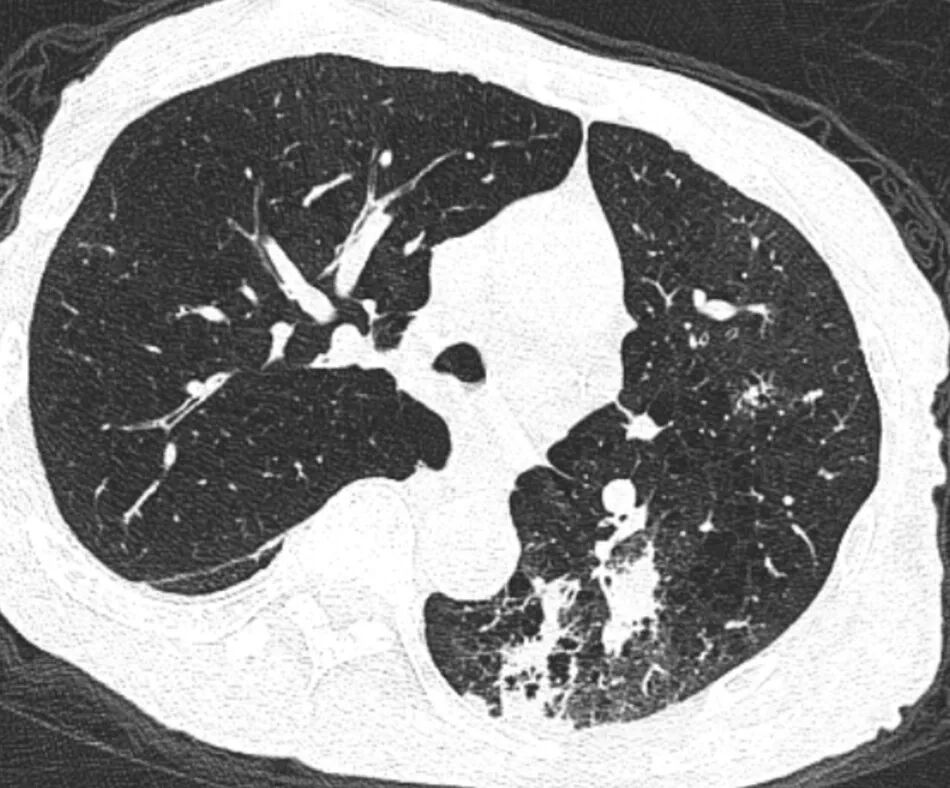

胸部CT提示存在肺部感染(图1)。

图1 胸部CT显示肺部斑片状感染灶